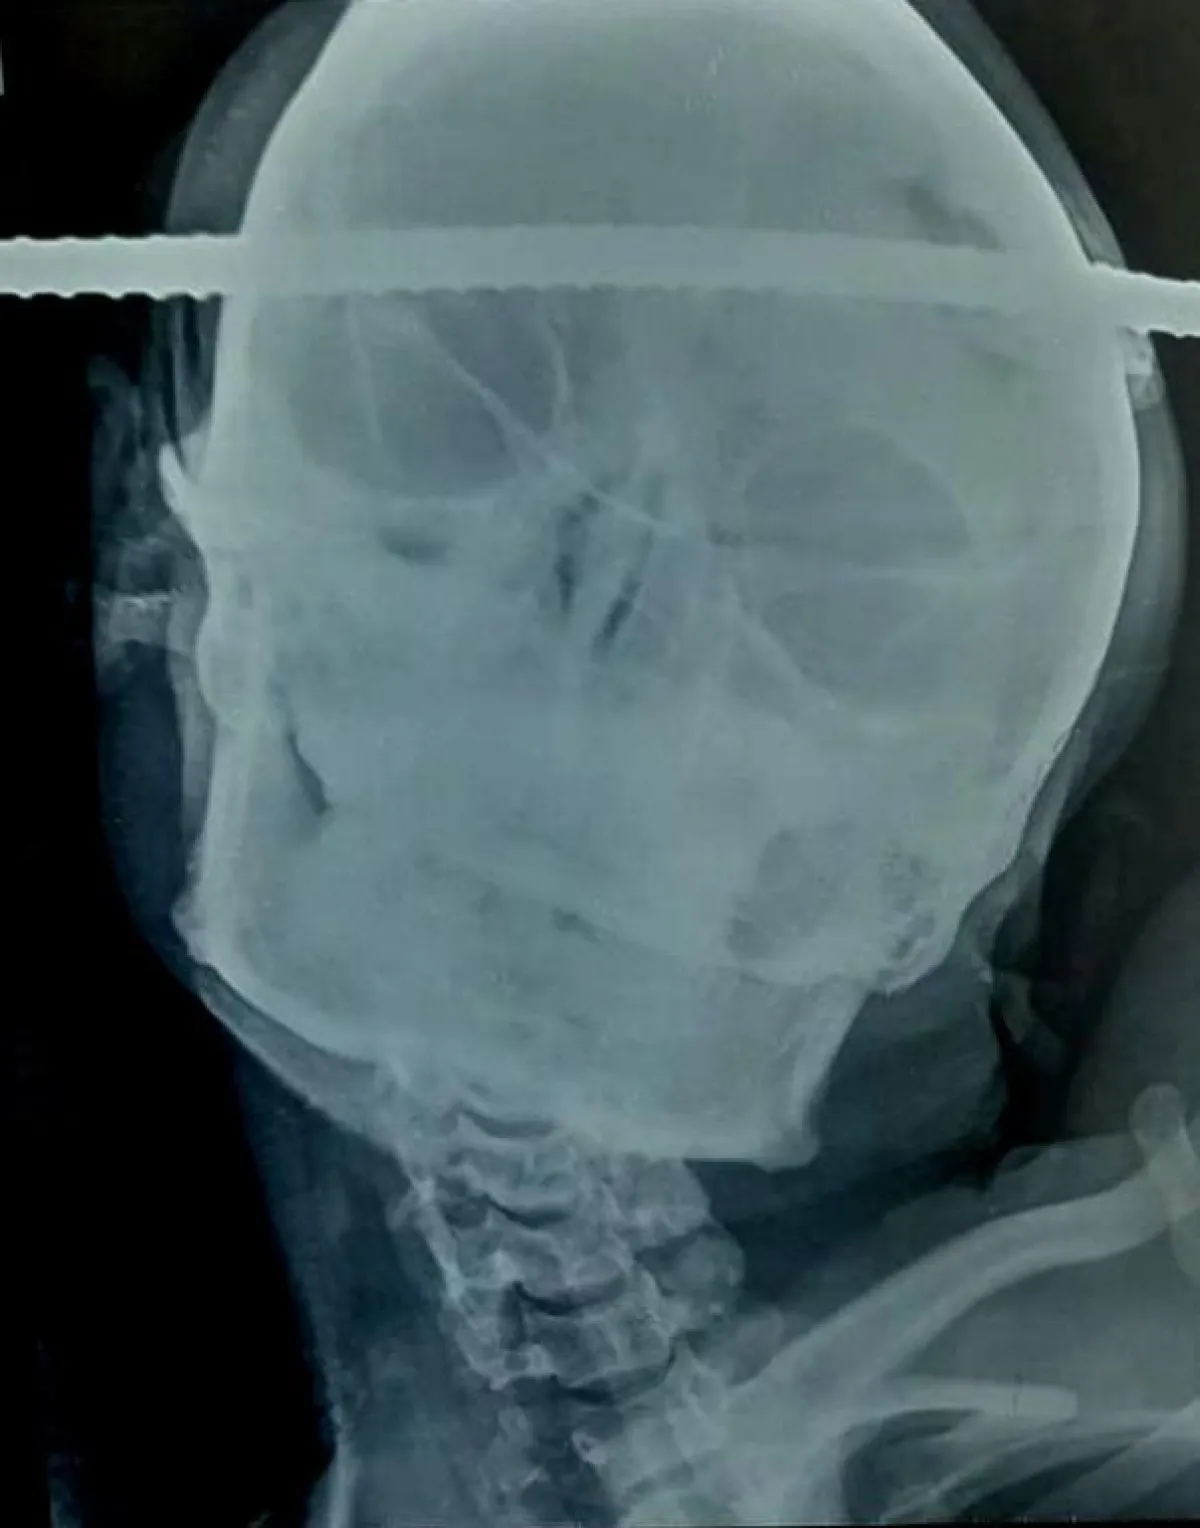

وبحسب ما نشره موقع «روسيا اليوم»، فقد نجا باهي من هذه الحادثة المميتة بعد سقوطه الخطير خلال قيامه ببناء بئر، حيث أسفر هذه السقوط عن اختراق «قضيب بناء حديد» للجهة اليُمنى من رأسه، ليخرج من الجهة اليُسرى، مسبباً أضراراً بالغة في جمجمته، بالإضافة إلى الكدمات الشديدة التي تعرضت لها يداه.

وتابع الموقع الروسي نقله لتفاصيل ما حدث مع العامل الهندي، أنه وخلال نقل سانجاي باهي بعد الحادثة إلى المستشفى، وخلال إجراء عملية جراحية طارئة له، كان لا يزال في وعيه كاملاً طوال هذا الوقت. على الرغم من أن العملية التي أجراها الأطباء استغرقت ما يزيد على الساعة والنصف «90 دقيقة»، والتي تم خلالها إزالة القضيب المعدني من جمجمته، حيث تبين أنه كان قد اخترق الفصَّ الصدغي الأيمن في المنطقة الأمامية اليسرى.

وفي تصريح لبرامود جيري، جراح الأعصاب الهندي الذي أجرى العملية الخطيرة، أدلى به لصحيفة الـ«ديلي ميل»، قال: «لقد بذلت كامل جهدي خلال العملية، لأكون في منتهى الحذر، حتى لا يحدث أي ضرر خطير لمناطق الدماغ المحيطة». مشيراً إلى أن مثل هذه العمليات من الصعب إجراؤها تحت التخدير.

وأضاف الدكتور أنه ولحسن حظ باهي، فقد كان القضيب بعيداً مسافة ميلليمترات قليلة فقط عن الأوعية الدموية الرئيسة داخل منطقة «القحف» في الدماغ، وهي المنطقة المسؤولة عن نقل المعلومات بين الدماغ وأجزاء الجسم الأخرى، وبشكل رئيس من وإلى الرأس والعنق، مبيناً أنه لم تحدث أي مضاعفات خلال الجراحة.